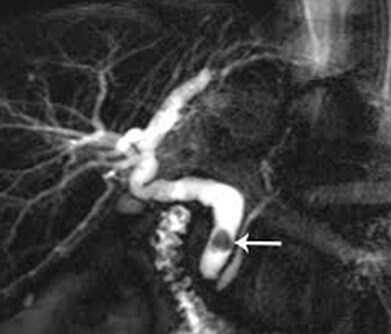

Ещё одним способом диагностики холедохолитиаза является магнитно-резонансная холангиопанкреатография (МРХПГ). Это высокоточный метод диагностики желчевыводящей системы и поджелудочной железы, который позволяет более чётко увидеть патологию желчной системы. Контрастное усиление повышает качество диагностики, при этом метод остаётся абсолютно безопасным для пациента. Такой вид МРТ проводят:

- для уточнения диагноза патологии желчевыводящей системы, которая включает в себя печень, желчный пузырь, внутрипечёночные и внепечёночные желчные протоки;

- при диагностике камней желчного протока, которые нельзя увидеть при рентгене;

- при подозрении на наличие опухолей в желчных протоках и протоке поджелудочной железы [13][14] .

Магнитно-резонансная томография позволяет увидеть внутри- и внепеченочные жёлчевыводящие протоки, а также главный панкреатический проток. К этому методу диагностики прибегают при подозрении о наличии конкрементов в общем жёлчном протоке. Это необходимо для планирования лечения.

На рисунке стрелкой обозначен конкремент в общем жёлчном протоке. При помощи дуоденоскопа в двенадцатиперстной кишке выполнено рассечение сфинктера Одди. Введено рентгеноконтрастное вещество, позволяющее визуализировать конкремент. При помощи специальной корзинки, выполняется захват и извлечение конкремента.